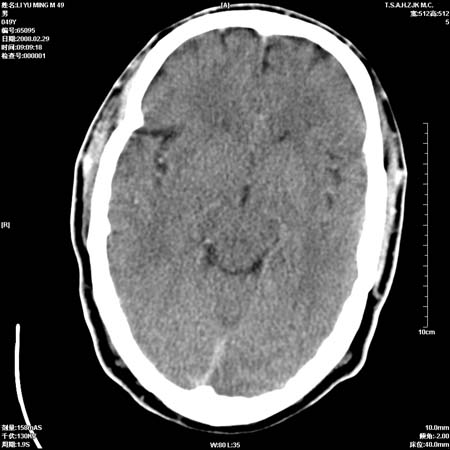

一周后复查ct:

可能为正常。间隔一周蛛血应基本吸收;再过一周复还是这样应该可以肯定了。

一周时间密度未见改变,考虑为正常图像(脑动脉硬化?)。